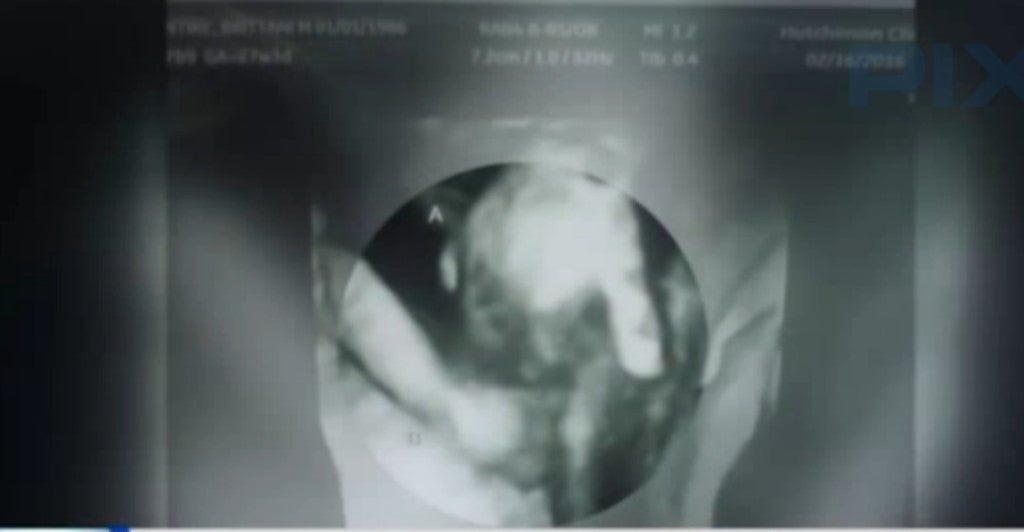

A recent sonogram showed Mason’s hand clasped around Madilyn’s.

“I know I’m holding him, I know I’m carrying him, but I just want to be there for him … she’s the only one that can actually be there and holding on to him through it,” said McIntire.